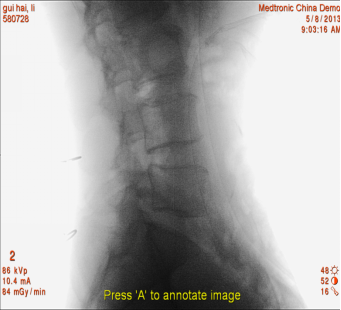

(1)患者采用俯卧位,提前设置好O型臂多维外科成像系统所需扫描定位平面(图1,图2),在正位透视下标定一条腰椎棘突中线,再沿髂棘最高点做一水平线,腰5骶1椎间盘正侧位的透视交叉点,即为穿刺点,一般在中心线旁开10-12cm左右处选一穿刺点。此线为穿刺的方向和角度(图3)。

图2 定位椎间隙 侧位